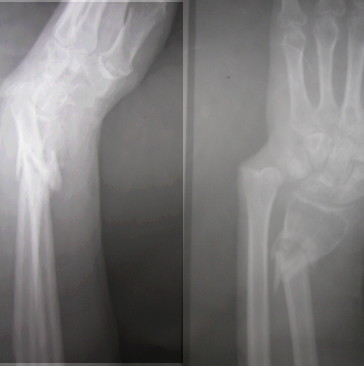

Dear All,Presenting this on behalf of a colleague of mine.52 years old healthy male sustained a closed fracture of his distal forearm 3 mths ago.

Due to so many other injuries sustained by him, this has been inadequately treated and he has ended up today like this. Very prominent distal ulna and a mobile fracture distal radius. No infection. Wrist flexion, extension fully free and so also the fingers. He has a good grip too. He wants correction of this deformity.I have opined as follows. Exfix with two pins in the distal radius and two proximally. Distract gradually till the DRUJ is properly aligned. 1)If one is lucky some bone would have formed in between which may be good enough. Continue ExFix till it is solid. 2) If we find that no bone is forming by 2 weeks, we can distract a bit faster Once the DRUJ is aligned and there is gap left, we can put in a small piece of fibula under tension and continue the ExFix till it is consolidated. If one is used to, a plate can be used to fix the radius along with the graft. This will shorten the ExFix time Suggestions are welcomeV M Iyer. Iyer Orthopaedic Centre, 103,Railway lines Solapur India

The image has been cropped and so it is not possible. The forearm and the elbow do not show anything abnormal,